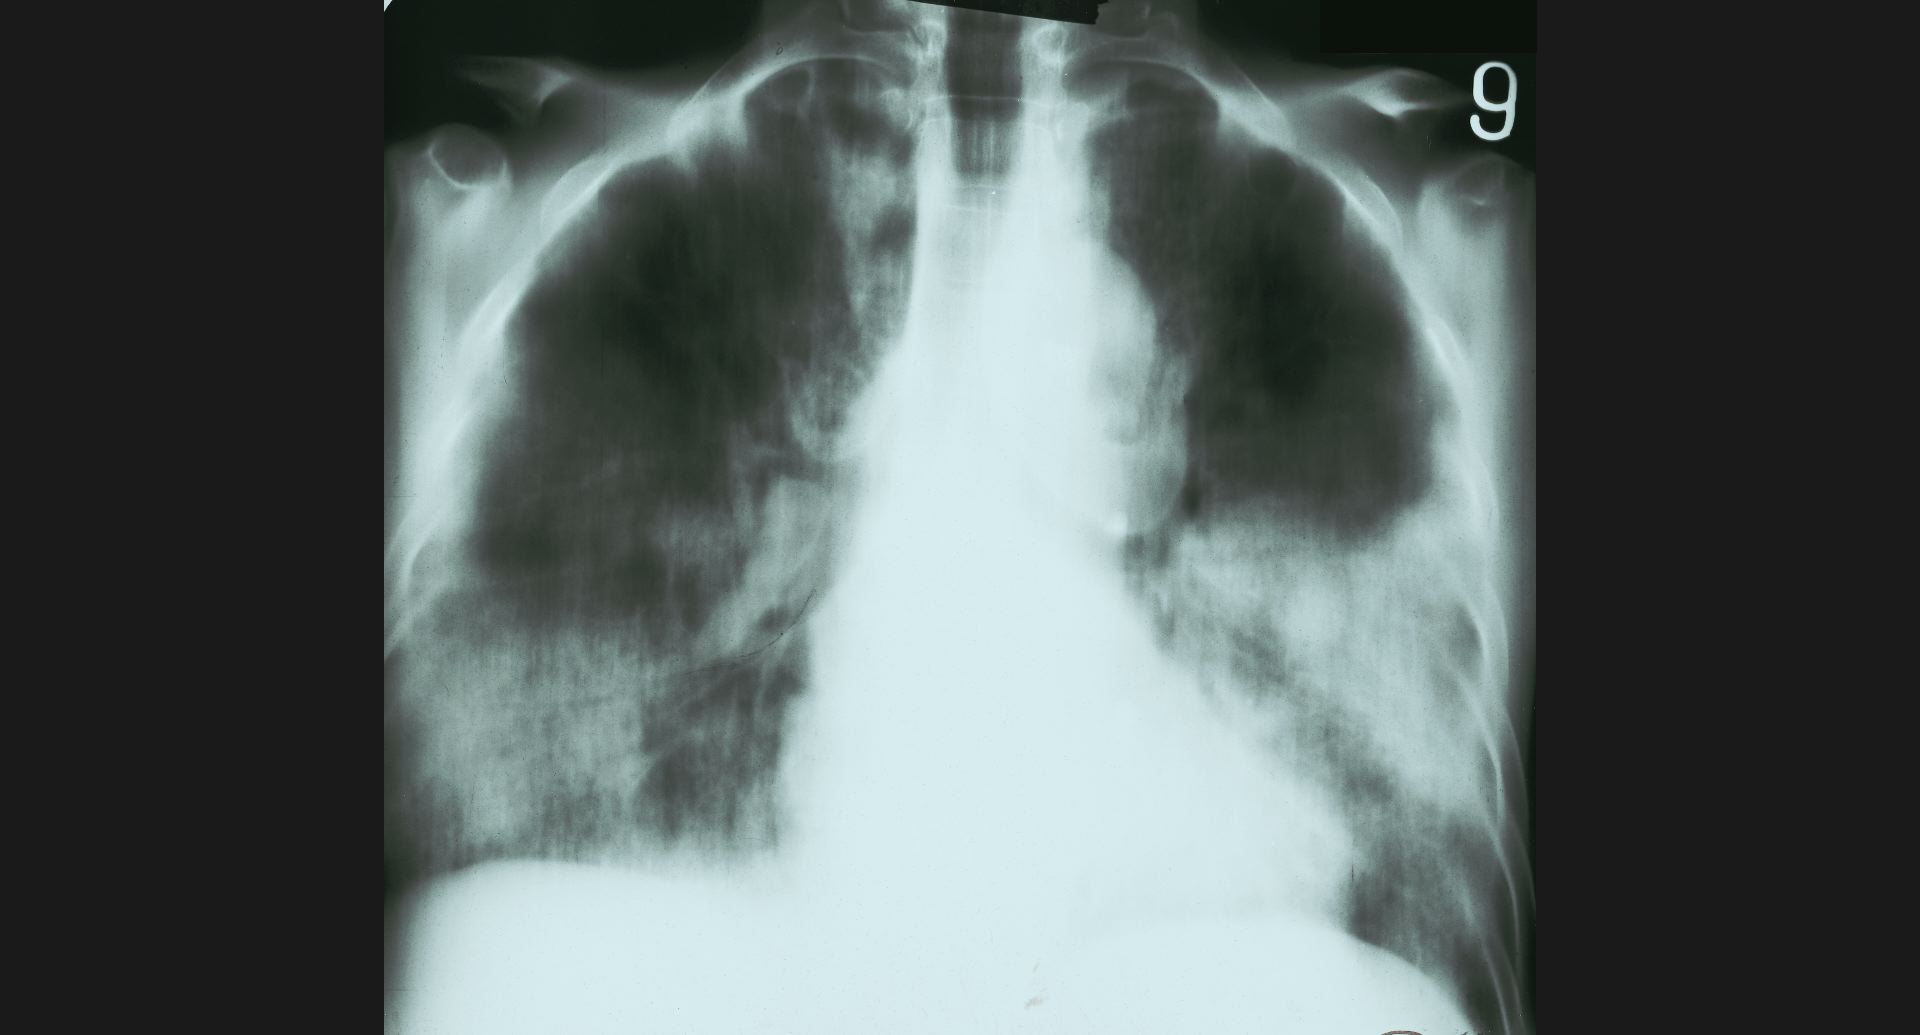

fig.9(94KB)

:Pneumoconiosis細かい斑状陰影。